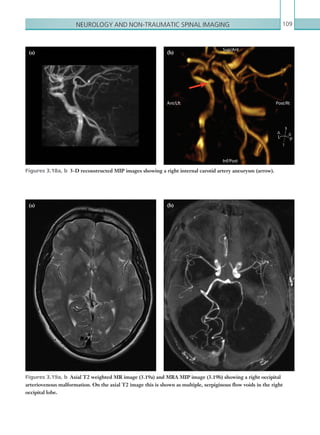

• 15.

Contents xi Key points145 Report checklist 145 MECONIUM ILEUS 145 Radiological investigations 145 Radiological findings 146 Lower gastrointestinal contrast study 146 Plain films 146 Key points 147 Report checklist 147 DUODENAL ATRESIA 147 Radiological investigations 147 Radiological findings 148 Plain films 148 Upper gastrointestinal contrast study 149 Key points 149 Report checklist 149 HYPERTROPHIC PYLORIC STENOSIS 149 Radiological investigations 149 Radiological findings 150 Ultrasound150 Key points 151 Report checklist 151 ORBITAL AND PERIORBITAL CELLULITIS 151 Radiological investigations 151 Radiological findings 152 Computed tomography 152 Key points 153 Report checklist 153 ACUTE OTITIS MEDIA 154 Radiological investigations 154 Radiological findings 154 Computed tomography 154 Key points 155 Report checklist 155 Reference155 PARAPHARYNGEAL AND RETROPHARYNGEAL ABSCESS 156 Radiological investigations 156 Radiological findings 157 Computed tomography 157 Key points 159 Report checklist 159 Reference159 K22247_FM.indd 11 16/05/15 3:05 AM

• 16.

Contentsxii CHAPTER 5: TRAUMAIMAGING 161 INTRODUCTION TO IMAGING IN MAJOR TRAUMA 161 Penetrating injury 163 Active haemorrhage 163 Blunt injury 166 Key points 166 Reference166 MAJOR TRAUMA: THORAX 167 Radiological investigations 167 Radiological findings 168 Mediastinal injury 168 Cardiac injury 168 Pneumothorax169 Haemothorax170 Rib fracture and flail chest 171 Lung contusion and lung laceration 172 Diaphragmatic injury 172 Key points 172 Report checklist 172 References172 MAJOR TRAUMA: ABDOMEN AND PELVIS 173 Radiological investigations 173 Radiological findings 174 Solid organ injury 176 Mesenteric and bowel injury 178 Pelvic injury 180 Bladder and urethral injury 180 Key points 182 Report checklist 182 References182 MAJOR TRAUMA: SPINE 182 Radiological investigations 183 Radiological findings 184 Plain films 184 Computed tomography 184 Magnetic resonance imaging 185 Examples of spinal fractures 185 Jefferson fracture 185 Odontoid peg fractures 186 Flexion teardrop fracture 186 K22247_FM.indd 12 16/05/15 3:05 AM

• 17.

Contents xiii Facet jointdislocation 187 Burst fracture 188 Key points 189 Report checklist 189 Reference189 CHAPTER 6: INTERVENTIONAL AND VASCULAR IMAGING AND IATROGENIC COMPLICATIONS 191 ACUTE ARTERIAL ISCHAEMIA 191 Radiological investigations 191 Radiological findings 192 Computed tomography 192 Key points 193 Report checklist 193 IATROGENIC COMPLICATIONS 193 NASOGASTRIC TUBE MISPLACEMENT 193 Radiological investigations 194 Radiological findings 194 Plain films 194 Key points 194 ENDOTRACHEAL TUBE MISPLACEMENT 195 Radiological investigations 195 Radiological findings 196 Plain films 196 Key points 196 ENDOVASCULAR STENT ENDOLEAK 197 Radiological investigations 197 Radiological findings 197 Computed tomography 197 Key points 198 Reference198 COMPLICATIONS OF COMMON FEMORAL ARTERY PUNCTURE 199 Radiological investigations 199 Radiological findings 200 Ultrasound200 Computed tomography 200 Key points 201 Appendix 1: NICE head injury guidelines 203 Appendix 2: Standards of practice and guidance for trauma radiology in severely injured patients 205 Appendix 3: Trauma computed tomography primary assessment 213 Index215 K22247_FM.indd 13 16/05/15 3:05 AM

• 18.

xiv Clinical radiology isat the centre of modern medicine and a high-quality service has repeatedly been shown to significantly improve patient outcomes. Over the last 10 years there has been a significant increase in demand for radiology services, resulting in a 26.5% increase in radiology examinations in England, from just over 30 million in 2004/5 to almost 39 million in 2010/11. Since 2004/5 the number of computed tomographic (CT) examinations has increased by 86% (Department of Health, 2011). On-call work, unsurprisingly, has followed this same trend with an increase in both the number and the complexity of scans now being performed out of hours as emergency imaging. Understandably, starting on calls in radiology can be a very daunting prospect. It marks a turning point from having very few responsibilities within a department to being integral to the work of both the Radiology Department and to the Hospital as a whole. On-call work presents a myriad of complex issues including: identifying pathology that may never have been seen before; coordinating scans and deciding scan protocols; and communicating with clinicians at all levels of seniority. Perhaps most importantly, on-call work carries a significant amount of responsibility since frequently, a decision on whether a patient needs to go to theatre or whether he/she requires immediate intervention will be dependent upon the findings of the radiology examination. PREFACE The purpose of this book is to try to assist junior radiology trainees who are starting their on calls. We have presented here the commonest cases that trainees are likely to encounter in an on-call situation. An almost limitless number of cases could have been included, since virtually anything can present in an on-call situation. We have, however, tried to present some of the most common cases as well as a host of tips on how to approach emergency imaging situations. Multiple images, as well as tips about reporting, have been included with each case. The majority of on-call work is CT work, and for this reason we have included CT scan protocols where appropriate. Although Radiology Departments have standard protocols for imaging of non-emergency work, the out of hours types of pathology sometimes require fine tuning of these protocols to ensure that appropriate sequences have been obtained. We hope that this text will assist junior radiology trainees in gaining some confidence as they start their on calls and will help assuage some of their fears. Gareth Lewis Hiten Patel Sachin Modi Shahid Hussain K22247_FM.indd 14 16/05/15 3:05 AM